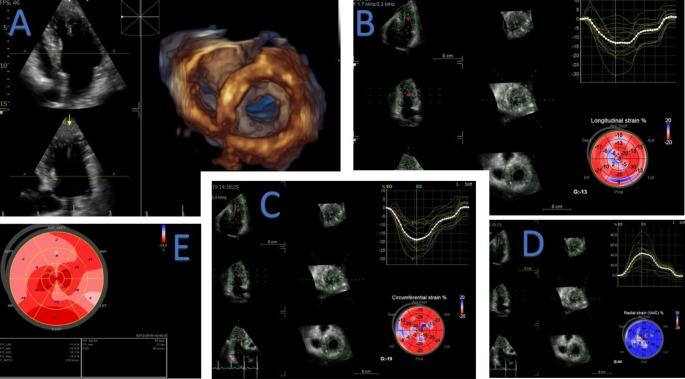

Patients with hypertrophic cardiomyopathy may exhibit impaired functional capacity, associated with increased morbidity and mortality. Systolic function is one of the determinants of functional capacity. Early identification of systolic disfunction may identify patients at risk for adverse outcomes. Myocardial deformation parameters, derived from three-dimensional (3D) speckle-tracking echocardiography (3DSTE) are useful tools to assess left ventricular systolic function, and are often abnormal before a decline in ejection fraction is seen. The aim of this study was to evaluate the correlation between myocardial deformation parameters obtained by 3DSTE and functional capacity in patients with hypertrophic cardiomyopathy. Seventy-four hypertrophic cardiomyopathy adult patients were prospectively evaluated. All patients underwent a dedicated 2D and 3D echocardiographic examination and cardiopulmonary exercise testing (CPET). Values of 3D global radial (GRS), longitudinal (3DGLS) and circumferential strain (GCS) were overall reduced in our population: 99% (n = 73) of the patients had reduced GLS, 82% (n = 61) had reduced GRS and all patients had reduced GCS obtain by 3DSTE. Average peak VO was 21.01 (6.08) ml/Kg/min; 58% (n = 39) of the patients showed reduced exercise tolerance (predicted peak VO < 80%). The average VE/VCO slope was 29.0 (5.3) and 16% (n = 11) of the patients had impaired ventilatory efficiency (VE/VCO > 34). In multivariable analysis, 3D GLS (β = 0.10, 95%CI: 0.03;0.23, p = 0.014), age (β = -0.15, 95%CI: -0.23; -0.05, p = 0.002) and female gender (β = -5.10, 95%CI: -7.7; -2.6, p < 0.01) were independently associated with peak VO. No association was found between left ventricle ejection fraction obtain and peak VO (r = 0.161, p = 0.5). Impaired myocardial deformation parameters evaluated by 3DSTE were associated with worse functional capacity assessed by peak VO.

肥厚型心肌病患者的功能能力可能受损,与发病率和死亡率增加相关。收缩功能是功能能力的决定因素之一。早期识别收缩功能障碍可识别出有不良结局风险的患者。源自三维斑点追踪超声心动图(3DSTE)的心肌变形参数是评估左心室收缩功能的有用工具,并且在射血分数下降之前往往是异常的。本研究的目的是评估 3DSTE 获得的心肌变形参数与肥厚型心肌病患者功能能力之间的相关性。74 例肥厚型心肌病成年患者前瞻性评估。所有患者均接受了专用的 2D 和 3D 超声心动图检查和心肺运动试验(CPET)。我们的人群中,3D 整体径向应变(GRS)、纵向应变(3DGLS)和周向应变(GCS)值均降低:73%(n=73)的患者 GLS 降低,61%(n=61)的患者 GRS 降低,所有患者 GCS 通过 3DSTE 获得均降低。平均峰值 VO 为 21.01(6.08)ml/Kg/min;58%(n=39)的患者运动耐量降低(预测峰值 VO<80%)。平均 VE/VCO 斜率为 29.0(5.3),16%(n=11)的患者通气效率受损(VE/VCO>34)。多变量分析中,3D GLS(β=0.10,95%CI:0.03;0.23,p=0.014)、年龄(β=-0.15,95%CI:-0.23;-0.05,p=0.002)和女性(β=-5.10,95%CI:-7.7;-2.6,p<0.01)与峰值 VO 独立相关。左心室射血分数与峰值 VO 之间无相关性(r=0.161,p=0.5)。3DSTE 评估的心肌变形参数受损与通过峰值 VO 评估的功能能力更差相关。